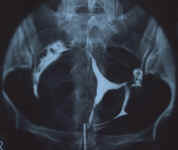

| Cavité utérine nettement grandie (8 x 2,5 x 6,5 cm). Les contours sont déformés par de multiples images lacunaires,la plupart arrondies, faisant ressembler la cavité utérine à "un morceau d'Emmenthal". La plus grosse de ces images lacunaires mesure 4 x 2 cm, elle est située sur la paroi latérale gauche de l'utérus. La cavité utérine elle-même est étirée, déformée, traduisant l'infiltration interstitielle associée aux multiples myomes sous-muqueux constatés. Les trompes sont perméables, de morphologie non déformée. Le passage intrapéritonéal est bon. Le brassage est excellent.

Conclusion:

Volumineux utérus polymyomateux, avec des formations interstitielles et sous-muqueusesTrompes perméables |    |